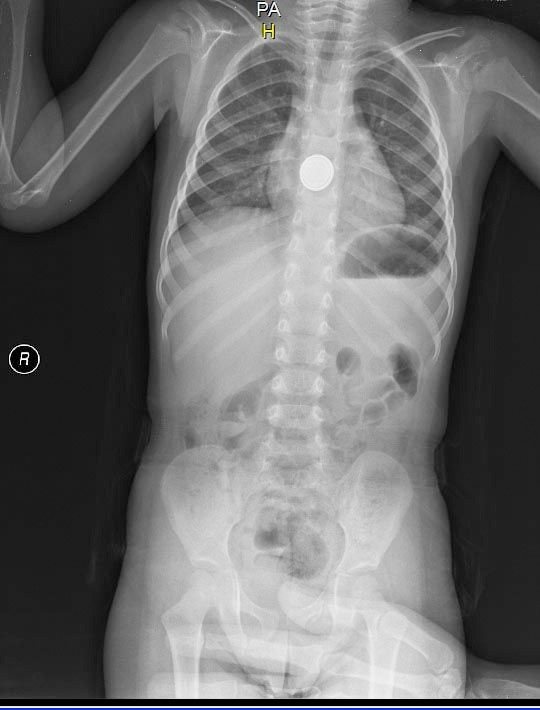

Küçük Efe pil yutunca olanlar oldu - Resim: 2

Küçük çocuk, ağzına aldığı pili yuttuktan kısa süre sonra yemek borusunda yanma hissetti. Annesinin yanına giden çocuk, 'Ben pil yuttum. Boğazım yanıyor' demesi üzerine ailesi tarafından hemen Medical Park Hastanesi Acil Servis'e götürüldü.

Acil Servis'te ilk müdahalesi yapılan ve filmi çekilen Mehmet Efe'yi ardından Gastroenteroloji Uzmanı Dr. Hüseyin Sancar Bozkurt'a yönlendirdi.

Bozkurt ve ekibi, endoskopik yöntemle yaklaşık yarım saatlik bir çalışmayla pili çocuğun boğazından çıkardı. Pilin çevresindeki dokuyu yakarak hasar verdiği belirlendi.